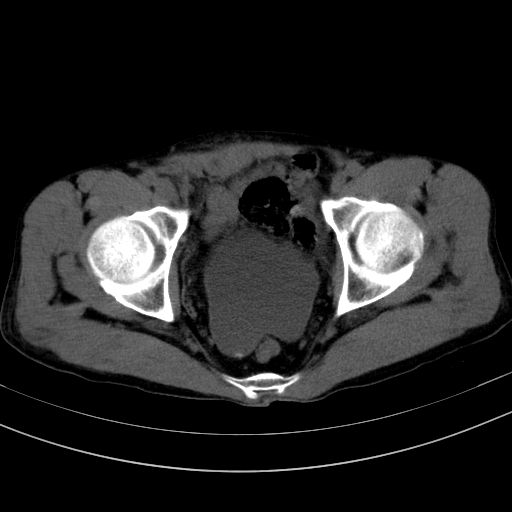

以下是引用37度在2010-1-9 14:37:00的发言:[br]1.双肾囊肿,左肾积水结石,.胆总管轻度扩张;[br]2.病灶在腹膜外,考虑纤维瘤。

以下是引用dyqct在2010-1-9 17:56:00的发言:[br]考虑:1.双肾囊肿,左肾积水结石、旋转不良。[br] 2.右侧腹直肌血肿或纤维瘤。[br]肠道准备不好。做个增强。